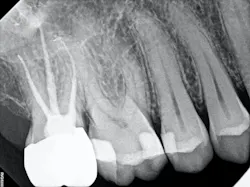

The carious tissue was removed, followed by the endodontic procedure and subsequent placement of the build-up. Despite the deep extent of mesial decay, a clear and accurate scan was achieved (figure 2).

The iTero scanner was able to clearly define the delineation between the soft and hard tissue as can be seen in this image of the digital die trim (figure 3). Radiographs were captured on delivery revealing a clinically acceptable outcome for the patient (figure 4). Direct restorations were completed on teeth Nos. 3 and 4 during this visit.